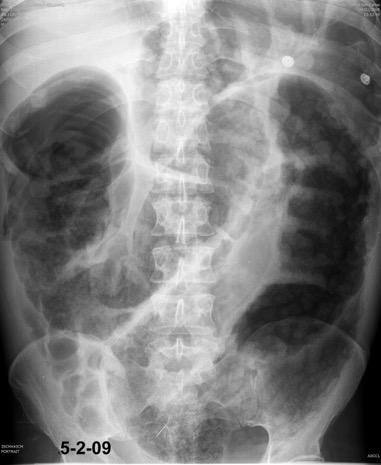

28. ELEVACIÓN UNILATERAL. OBSTRUCCIÓN INTESTINAL

Rx: Niveles hidroaéreos en hemitórax izquierdo Desviación mediastínica Ausencia de intestino en abdomen. Configuración en reloj de arena del intestino herniado “Tubo nasogástrico”

Furak J et al. Diaphragm and transdiaphragmatic injuries. J Thorac Dis 2019